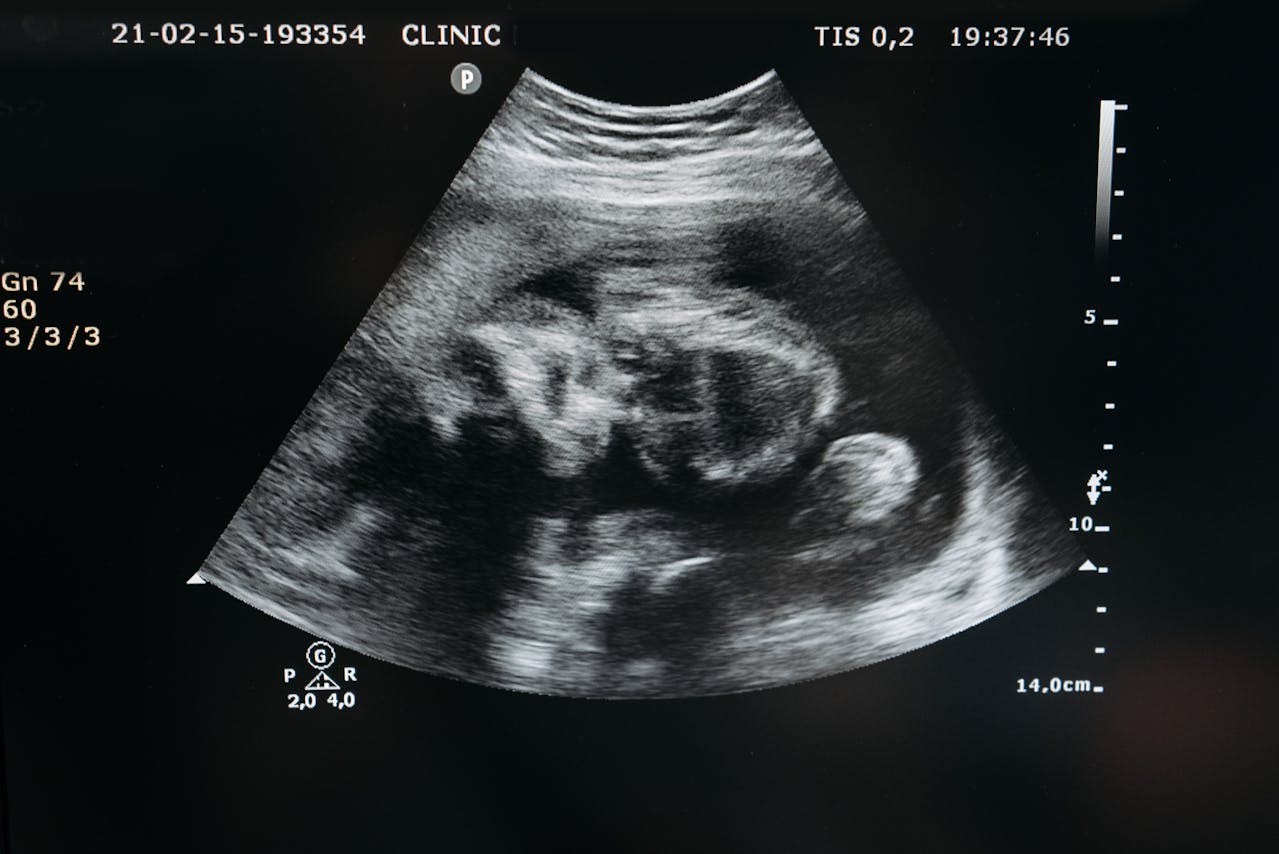

Desde el diagnóstico se hará el seguimiento conjunto con la Unidad de medicina fetal para un control seriado con ecografía-doppler.

Se define OLIGOAMNIOS como un volumen de líquido amniótico disminuido y se objetiva por una columna <2 cm medida por ecografía. Se asocia a diversas patologías obstétricas como retraso del crecimiento intrauterino, enfermedades genéticas, etc.

Se define POLIHIDRAMNIOS como un volumen de líquido amniótico aumentado y se objetiva por una columna >8 cm medida por ecografía. Se asocia igualmente a patología obstétrica como diabetes gestacional, cuadros malformativos fetales, etc.